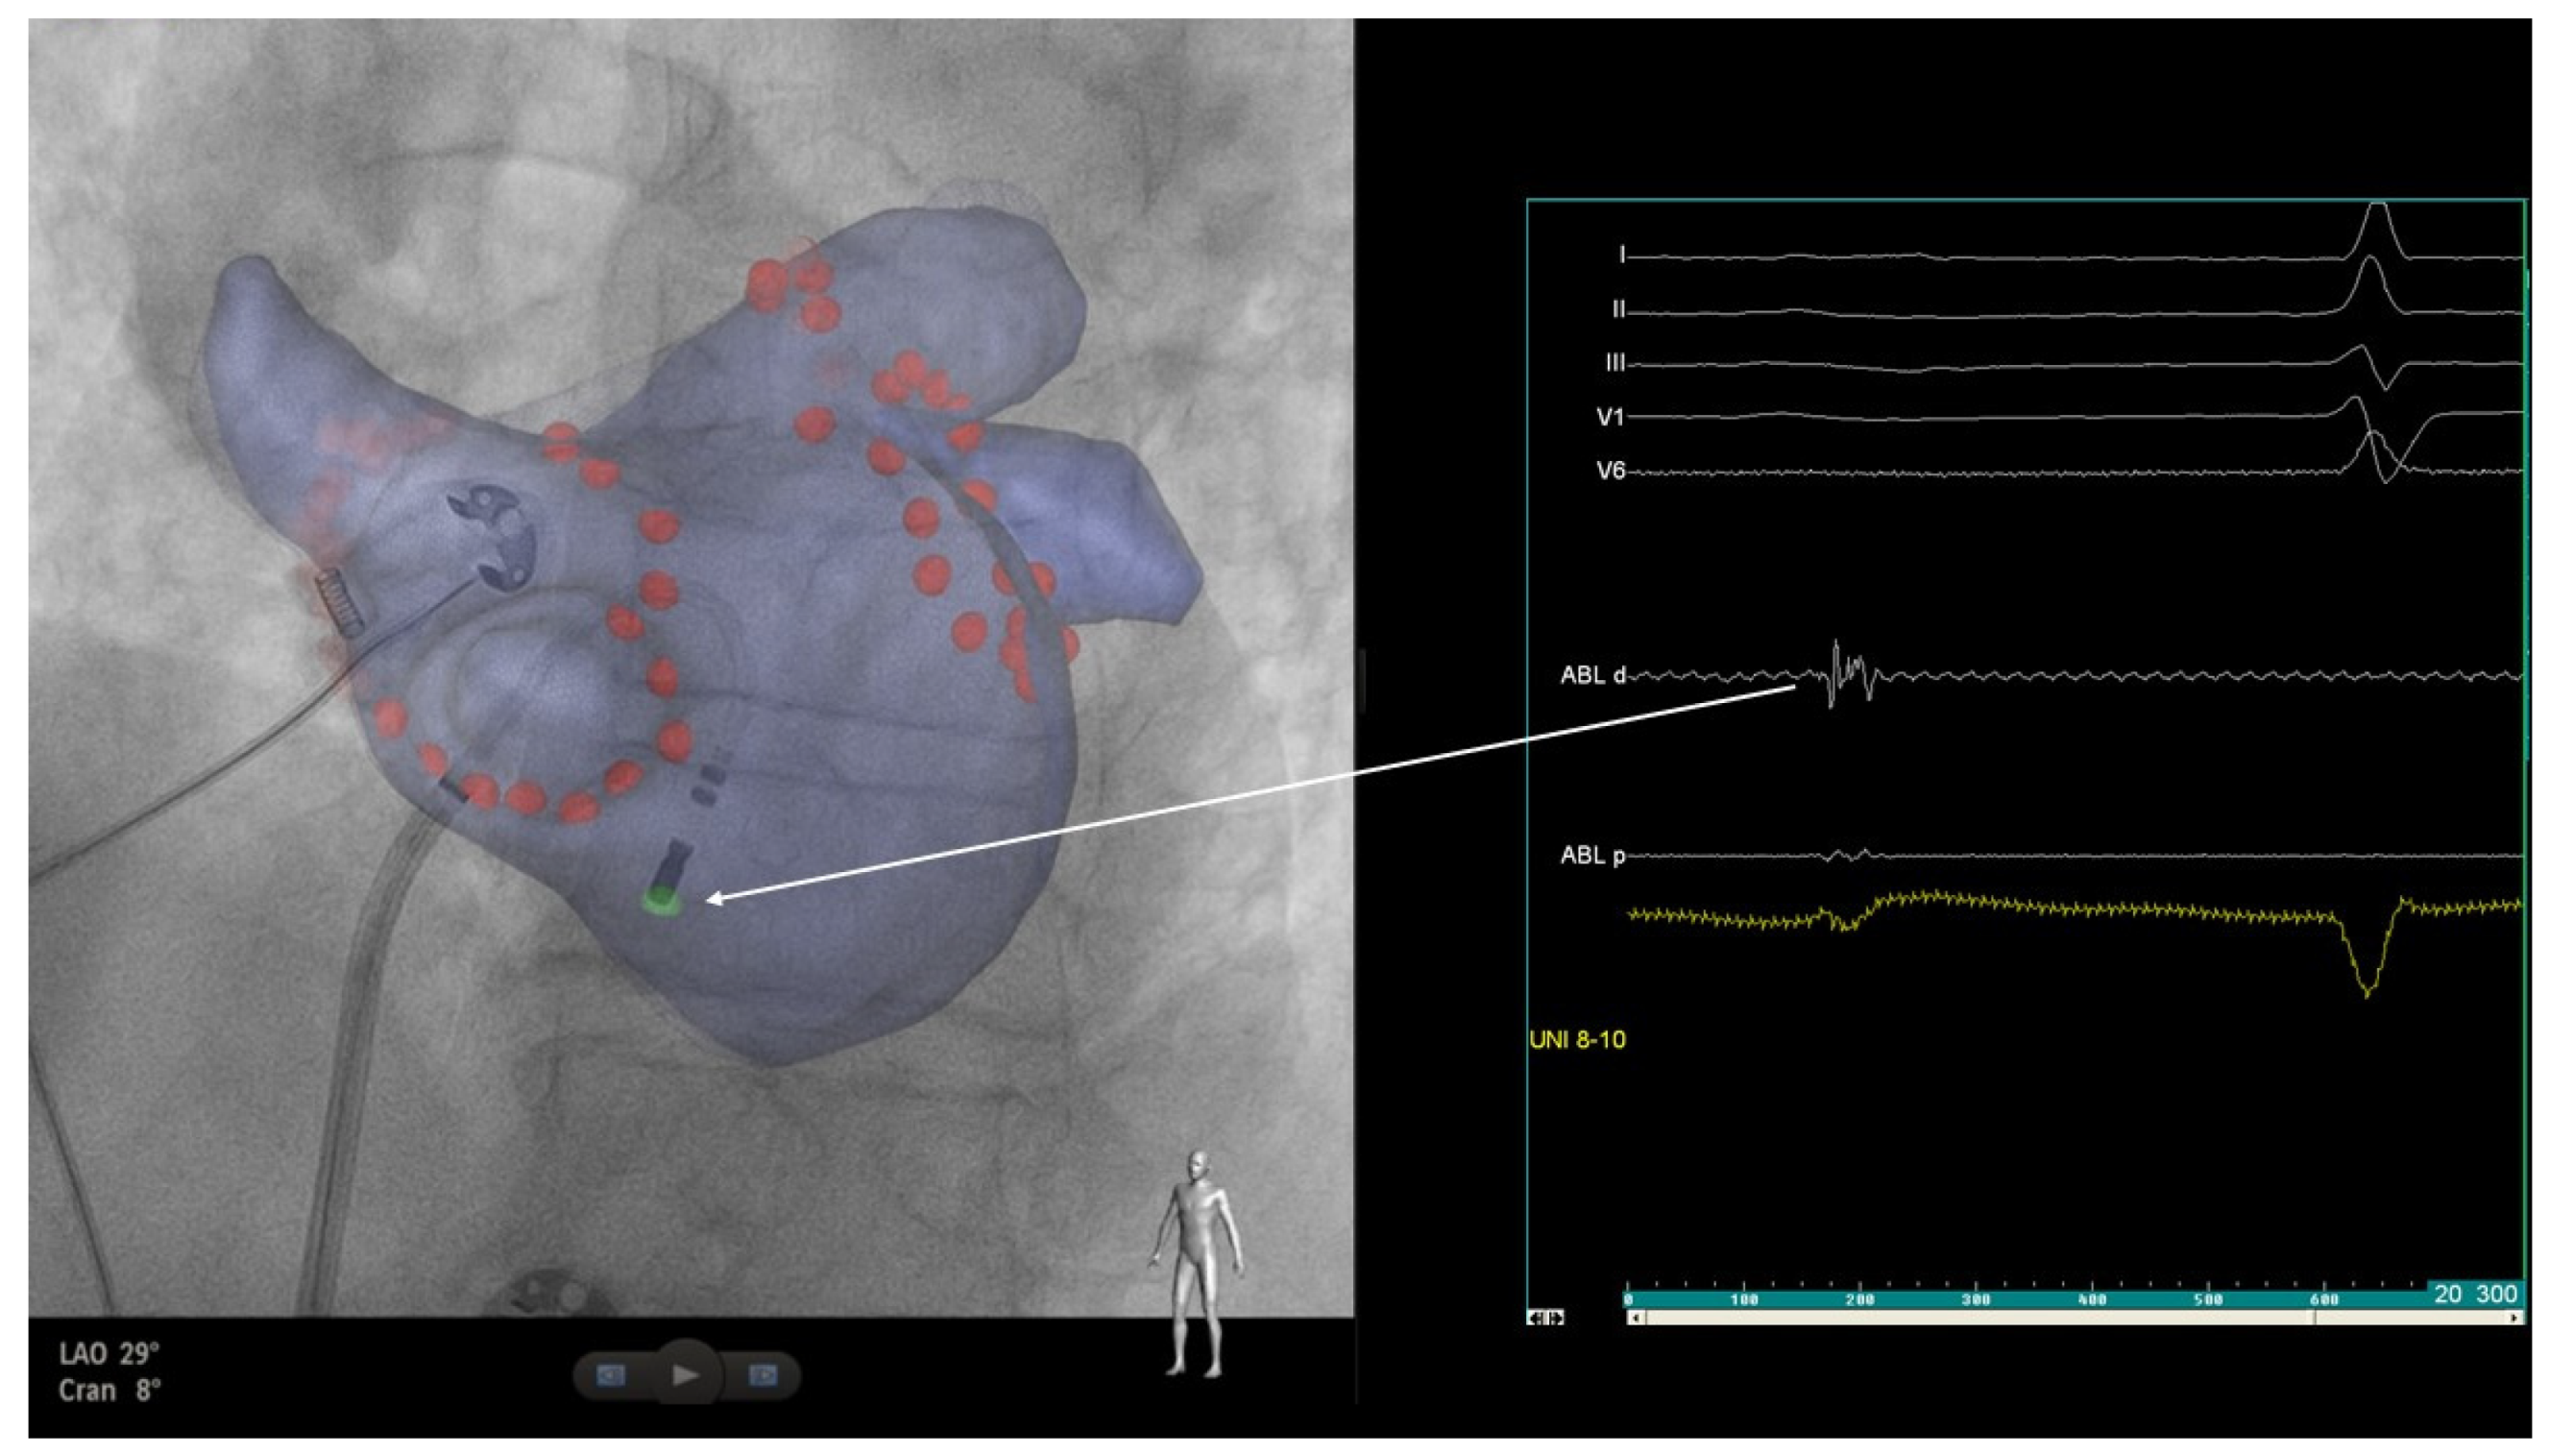

2. Case Report